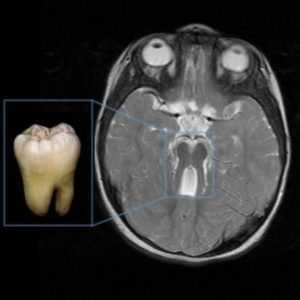

- нарушение в образовании и развитии мозжечка и ствола головного мозга, четко выявляемое на МРТ («синдром молярного зуба» или «molar tooth sign»);

Синдром молярного зуба и другие признаки болезни Жубера на МРТ:

Диагностика с помощью МРТ продемонстрирует развитие отделов головного мозга. У пациентов с данным диагнозом наблюдаются изменения, напоминающие разрез зуба («синдром коренного зуба»). Это свидетельствует о патологических изменениях стволовой части мозга и червя мозжечка. Другими признаками недоразвития мозга являются расширенные желудочки, гидроцефалия, недоразвитие мозжечка.

Самым типичным диагностическим признаком синдрома Жубер является наличие так называемого «симптома молярного зуба» - характерные изменения на МРТ головного мозга, внешне похожие на разрез зуба. Это проявление говорит о наличии нарушений формирования стволовых элементов мозга. Также на магнитно-резонансной томографии часто определяется недоразвитие червя мозжечка, гипоплазия мозолистого тела, гидроцефалия, расширение желудочков, энцефалоцеле и другие аномалии развития головного мозга. У взрослых больных синдромом Жубер нередко выявляются признаки поражения внутренних органов - поликистоз почек, фиброз печени, нарушения сердечного ритма. При осмотре у офтальмолога часто обнаруживаются непроизвольные аномальные движения глаз (нистагм), колобома, дистрофия и дегенерация сетчатки.

- симптом «коренного зуба»: на МРТ в аксиальной плоскости через точку соединения среднего мозга и моста (область перешейка) выявляются признаки гипоплазии червя мозжечка и сопутствующие аномалии ствола мозга. Признак «коренного зуба» включает в себя аномально глубокую межножковую ямку, заметные, прямые и утолщенные верхние ножки мозжечка и гипоплазию червя мозжечка;

Признак коренного зуба